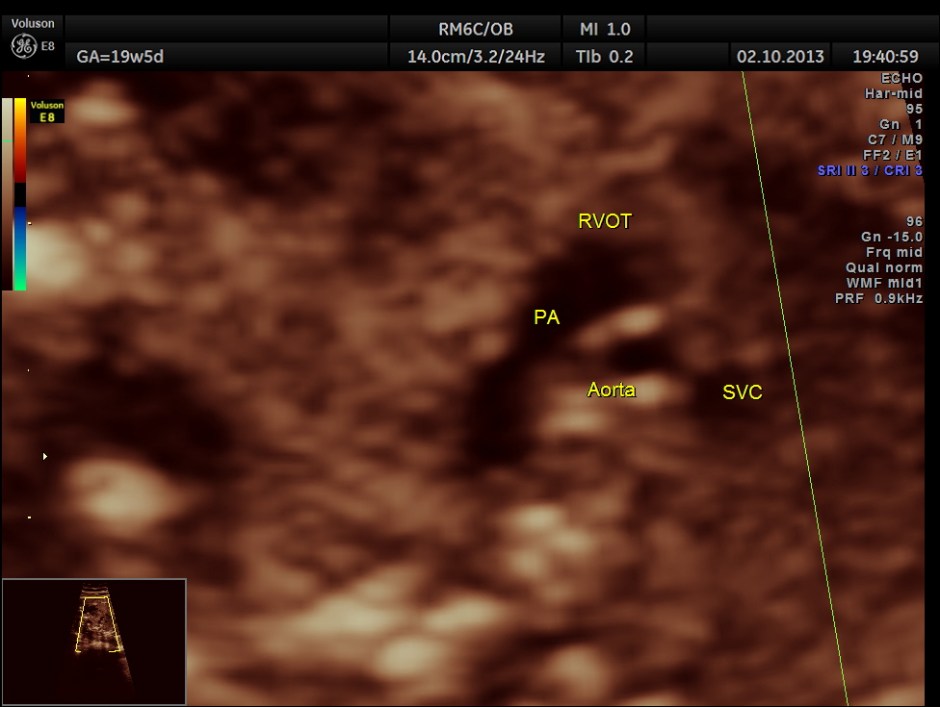

The following pictures show that the left ventricle appears smaller than the right ventricle. The situs is normal.

Colour flow also rules out the possibility of hypoplastic left heart syndrome.

The 4 chamber view is abnormal – LV is smaller than RV.

The 3 vessel trachea view depicts great vessel disproportion. Pulmonary artery is bigger than aorta .